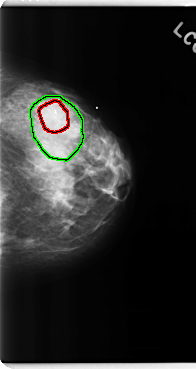

C_0272_1.LEFT_CC

LEFT_CC LINES 4792 PIXELS_PER_LINE 2536 BITS_PER_PIXEL 12 RESOLUTION 50 OVERLAY

FILE: C_0272_1.LEFT_CC.OVERLAY

TOTAL_ABNORMALITIES 2

ABNORMALITY 1

LESION_TYPE CALCIFICATION TYPE PLEOMORPHIC DISTRIBUTION CLUSTERED

ASSESSMENT 4

SUBTLETY 5

PATHOLOGY BENIGN

TOTAL_OUTLINES 1

BOUNDARY

ABNORMALITY 2

LESION_TYPE MASS SHAPE LOBULATED MARGINS OBSCURED

ASSESSMENT 3

SUBTLETY 3